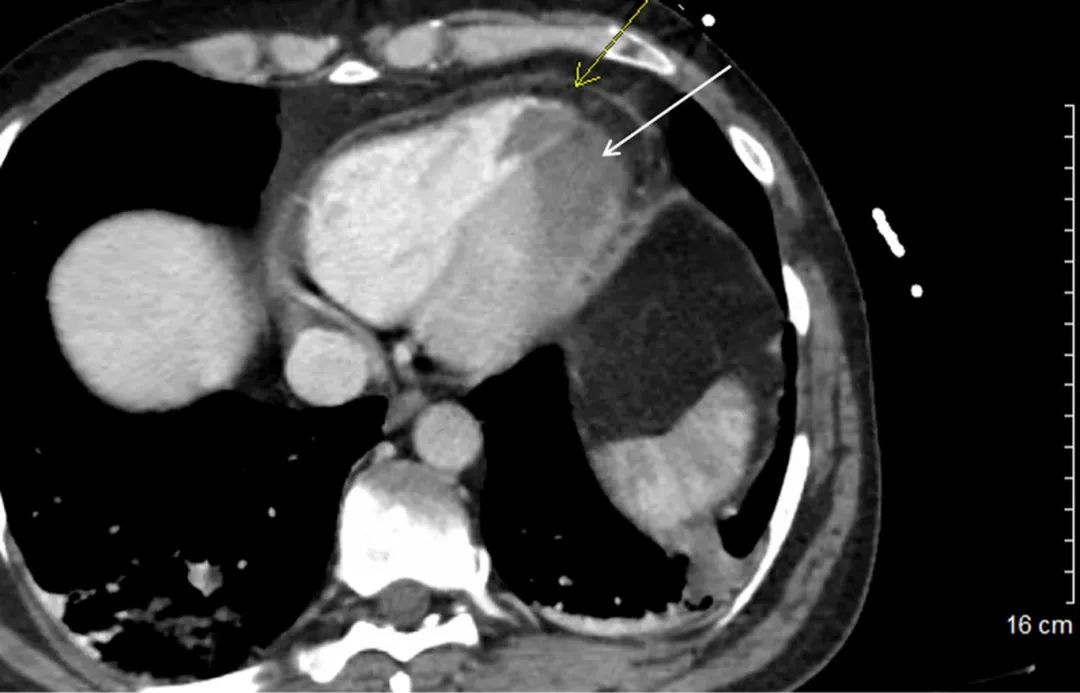

病史摘要:54 岁男性,因“呼吸困难 1 周”就诊,平卧位或活动时加重,休息缓解,无发热、咳嗽及下肢水肿,体温、生命体征平稳。既往有哮喘、高血压、糖尿病及终末期肾病血液透析病史。 诊疗过程:查体双肺呼吸音清,心脏听诊因体型受限。床旁肺部超声未见肺水肿或胸腔积液,床旁心脏超声显示连枷样主动脉瓣伴活动性高回声团块致主动脉瓣关闭不全,经食管超声心动图进一步证实,确诊为感染性心内膜炎导致连枷样主动